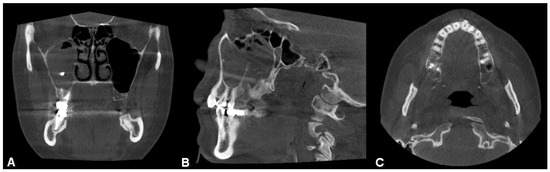

Figure 6. CBCT image of unilateral maxillary sinusitis and oro-antral fistula with the characteristic radiological image of fungal infection, which radiologically mimics foreign bodies ((A): coronal, (B): axial, (C): sagittal view).